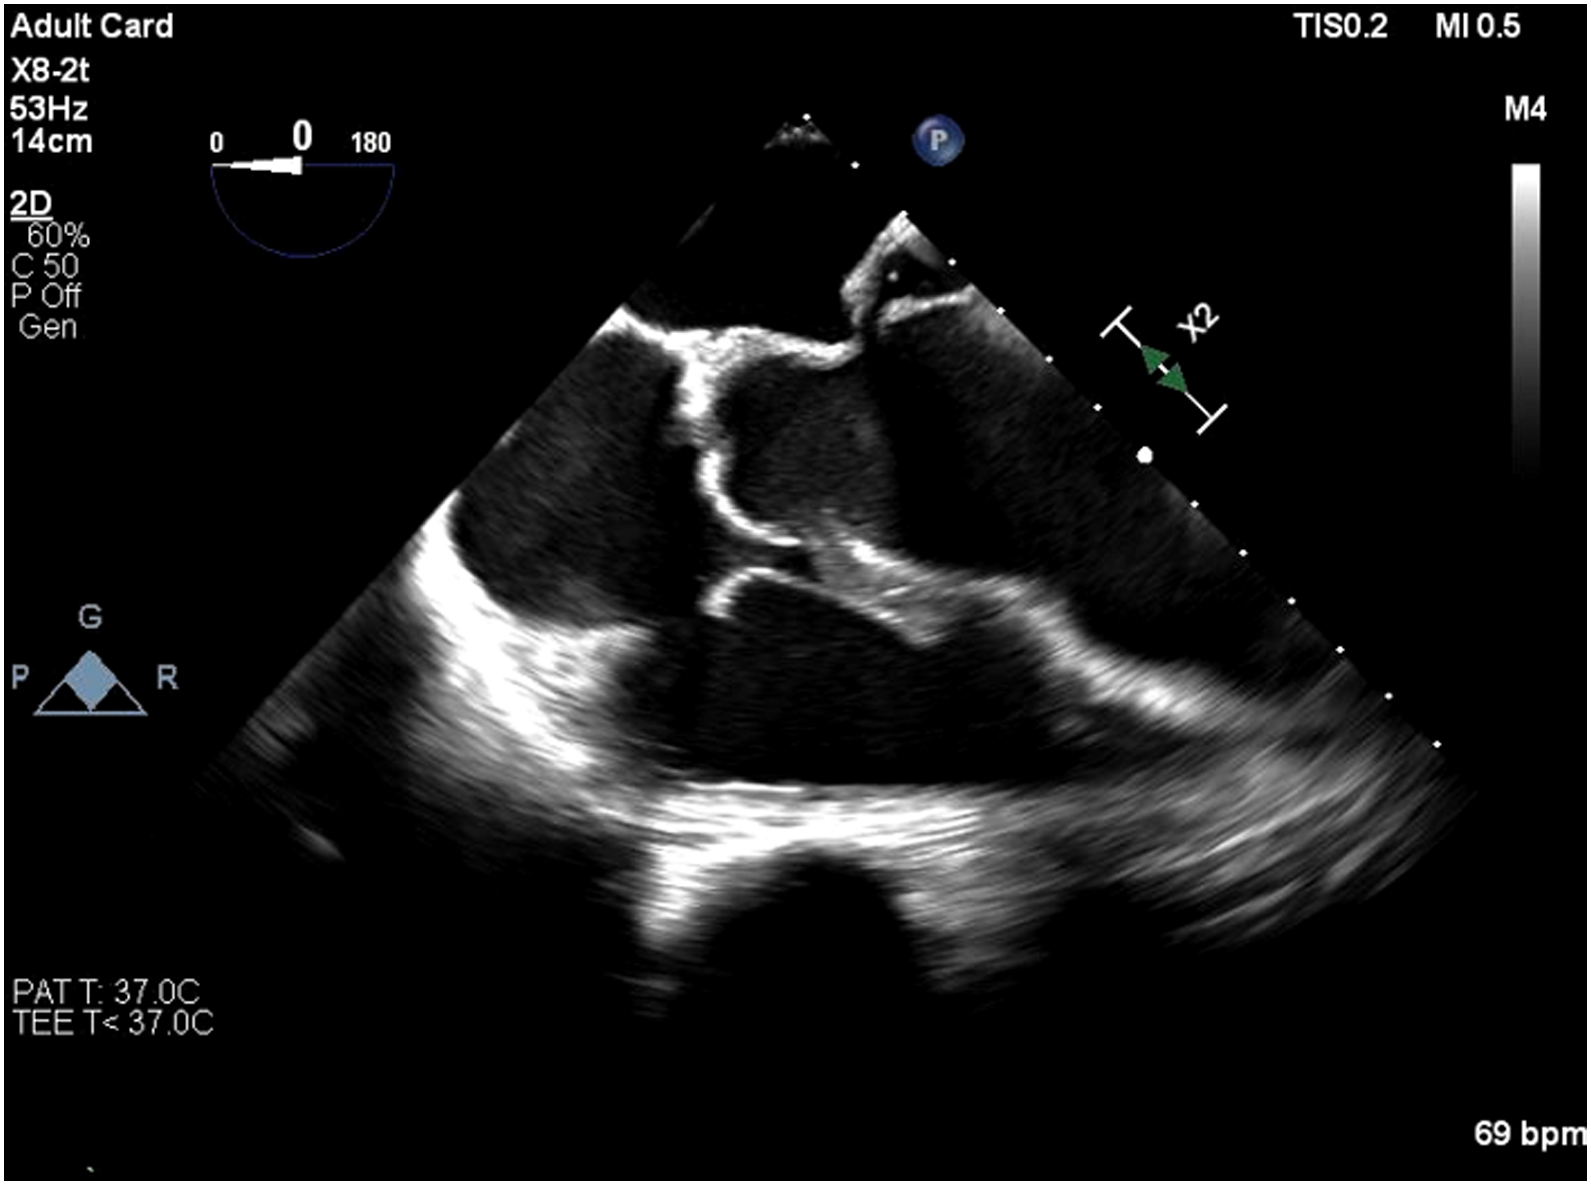

Echocardiogram showed impaired LV systolic function, global wall hypokinesia, normal prosthetic aortic valve function with mild paravalvular leakage and bulging of aortomitral intervalvular fibrosa, suspected

Aortomitral intervalvular fibrosa aneurysm.

CT cardiac revealed pseudoaneurysm of the aortomitral intervalvular fibrosa with laminated thrombus with no LAA thrombus visualized.